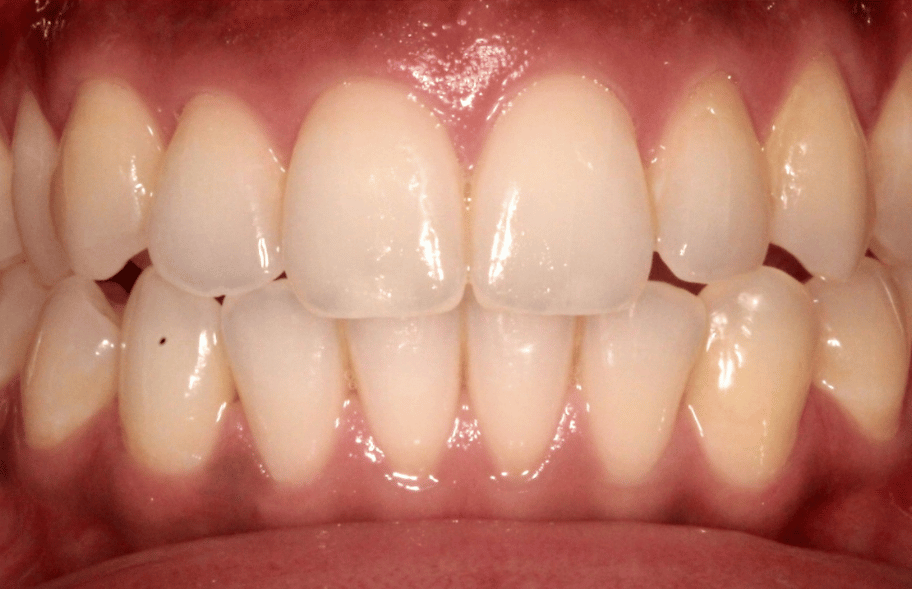

After

After